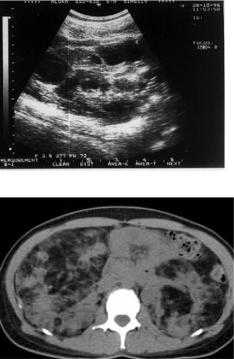

Ангиомиолипомы и кисты. Редко - карциномы. Нарушения со стороны почек, как правило, появляются на 2-м - 3-м десятилетии жизни. Ангиомиолипомы при туберозном склерозе множественные, двусторонние и длительное время имеют бессимптомное течение.

Ангиомиолипомы больше 4 см в диаметре имеют тенденцию к спонтанному кровоизлиянию. Основными клиническими симптомами кровоизлияния из ангиомиолипомы: острые абдоминальные боли, падение артериального давления. Кисты почек при туберозном склерозе чаще небольшого размера, двусторонние. При увеличении размера кист развивается почечная недостаточность, появляется высокое артериальное давление.

УЗИ. Кисты почки

На КТ множественные двусторонние образования в почках, содержащие жировую ткань - ангиомиолипомы.

МР оценка почечной ткани так же очень важна для диагностики и оценке течения заболевания. При УЗИ и МРТ в почках выявляются разнокалиберные кисты, липомы и ангиомиолипомы. Данные литературных источников ставят основной акцент на выявлении кист в почках, из-за близости мутаций при туберозном склерозе и поликистозе почек. Однако это не совсем так, основной акцент стоит уделять выявлению ангиомиолипом (АМЛ). Разделяют два их основных типа это АМЛ с низким содержанием жира и эпителиоидный АМЛ. Так как для пациентов с туберозным склерозом так же могут формироваться злокачественные образования (карциномы). Карциномы развиваются сами по себе, но они очень похожи на АМЛ с низким содержанием белка, поэтому эти АМЛ необходимо описывать их отдельно, чтобы не пропустить образование. Классические ангиомилипомы выглядят гиперинтенсивными на T1- и T2-взвешенных изображениях и гипоинтенсивными на T1-взвешенных изображениях.